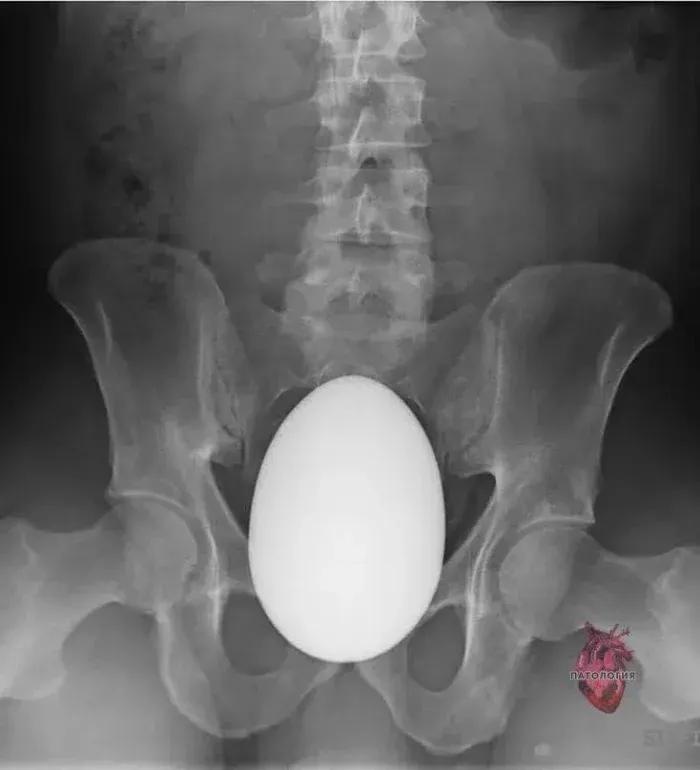

塞进去的东西就比较五花八门了,沐浴露、胡萝卜、鸵鸟蛋、水果刀、啤酒瓶,甚至还有活物……

由于部位的私密性,很多患者往往不会坦白病情,“每次接诊,就像是在开盲盒”。

一位不愿意透露姓名的肛肠科大夫表示:“除了孩子,好像啥都取出来过。”